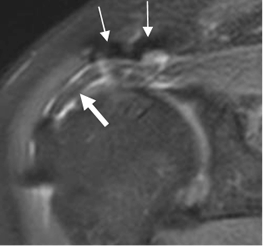

En el manguito reparado se aprecia irregularidad del tendón y señal baja o intermedia, por la cicatrización y fibrosis. (29). (Fig 159 y 160).

Fig 159. Cambios PostQx.

RM coronal en STIR. Cambios PostQx en la articulación acromioclavicular, que producen artefactos. (Flechas delgadas). Signos de tendinitis del supraespinoso, el cual está adelgazado y rodeado por líquido. (Flecha gruesa).